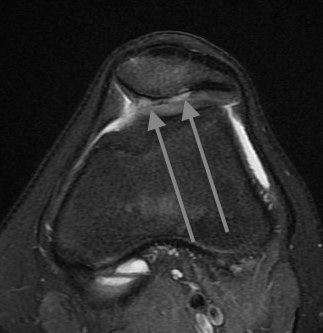

MRI

Lateral subluxation / trochlea dysplasia

Articular cartilage damage

TTTG